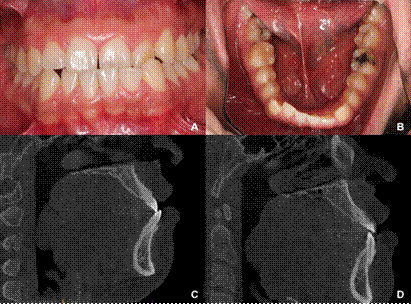

Su presentación más común es cuando los caninos muestran una versión excesiva, en donde un canino se inclina hacia vestibular y el otro hacia lingual o palatino mientras que el alambre de la contención fija permanece perfectamente adherido a ambos dientes 8. Al mismo tiempo, los incisivos se proyectan frontalmente, lo que lleva a una oclusión vis a vis y, en caso de periodonto delgado, a la exposición de la raíz (8.

En ocasiones, la versión canina, es inapreciable y es el incisivo el que muestra una versión radiculovestibular o coronovestibular muy marcada (8. En algunos casos, también los incisivos están desalineados y sus ejes inclinados junto con el canino comprometido, como se puede ver en la figura 2 y 3. En otros casos, donde la contención fue colocada solamente en los incisivos inferiores, son estos los que sufren los movimientos como se puede ver en la figura 4.